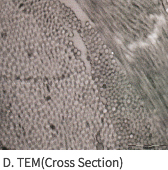

SEM Image (These have kept the collagen structure after the E-Beam sterilization.)

Mega-Derm Plus three-dimensional structure of the dermis

The world's first 'E-Beam' sterilization that does not destroy the collagen structure